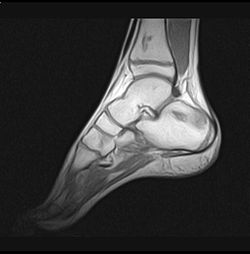

| Posttraumatische partielle Talusnekrose in der Magnetresonanztomographie (T1 FS mit Kontrastmittel). Man erkennt gut die praktisch signalfreie Zone lateral in der Talusrolle als Zeichen von Sklerose einerseits und fehlender Kontrastmittelaufnahme andererseits. | Eigenes Werk | Hellerhoff | Datei:Talusnekrose partiell posttraumatisch - MRT T1 FS KM.jpg |